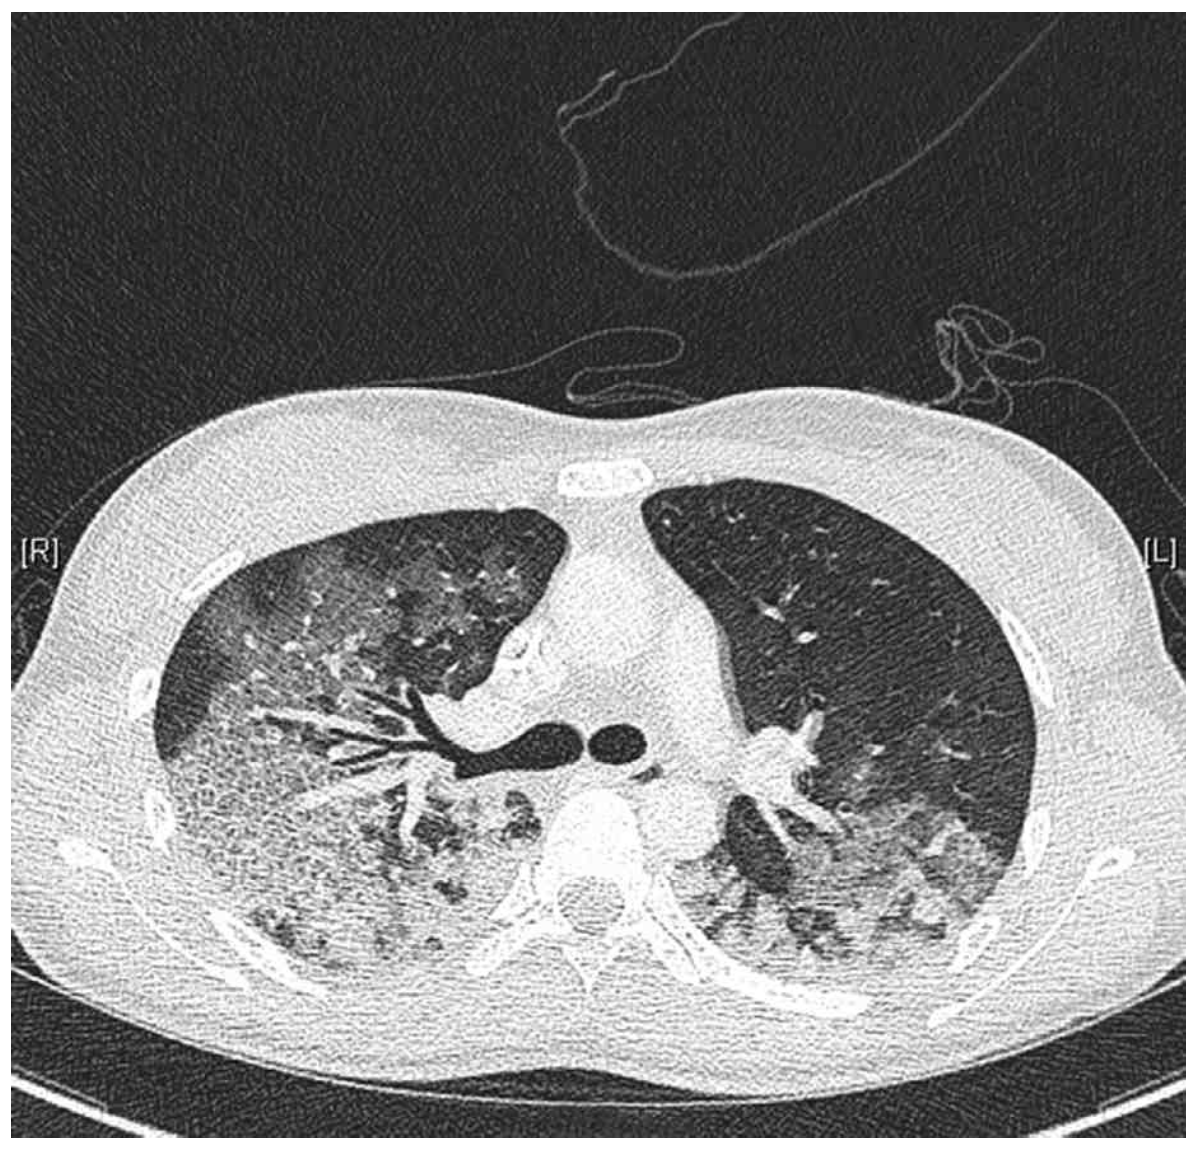

46세 여자가 2일 전부터 숨이 찬다며 병원에 왔다. 5일 전 콧물이 나고 근육통과 열감이 있었다. 3일 전부터 가래 섞인 기침을 하고 점점 심해졌다고 한다. 비흡연자이다. 혈압 80/50 mmHg, 맥박 116회/분, 호흡 36회/분, 체온 38.2°C 이다. 진찰 중에 자꾸 자려고 한다. 양쪽 가슴에서 거품소리가 들린다. 가슴 X선사진과 가슴 컴퓨터단층촬영 사진이다. 검사 결과는 다음과 같다. 처치는?

CT: Diffuse bilateral opacities and GGOs

• 더불어 1주일 이내 호흡증상이 시작되었고, CXR 및 chest CT 등 영상 소견에서 bilateral diffuse opacity를 관찰할 수 있으며, BNP가 참고치 이내로 심부전 및 체액 과부하의 증거가 없고 PaO2/FiO2 = 52/0.5~0.6 ≤ 300mmHg으로 hypoxemia가 확인된다. 따라서 해당 증례는 Berlin definition의 네 가지 기준을 모두 만족하므로 급성호흡곤란증후군으로 진단할 수 있다.